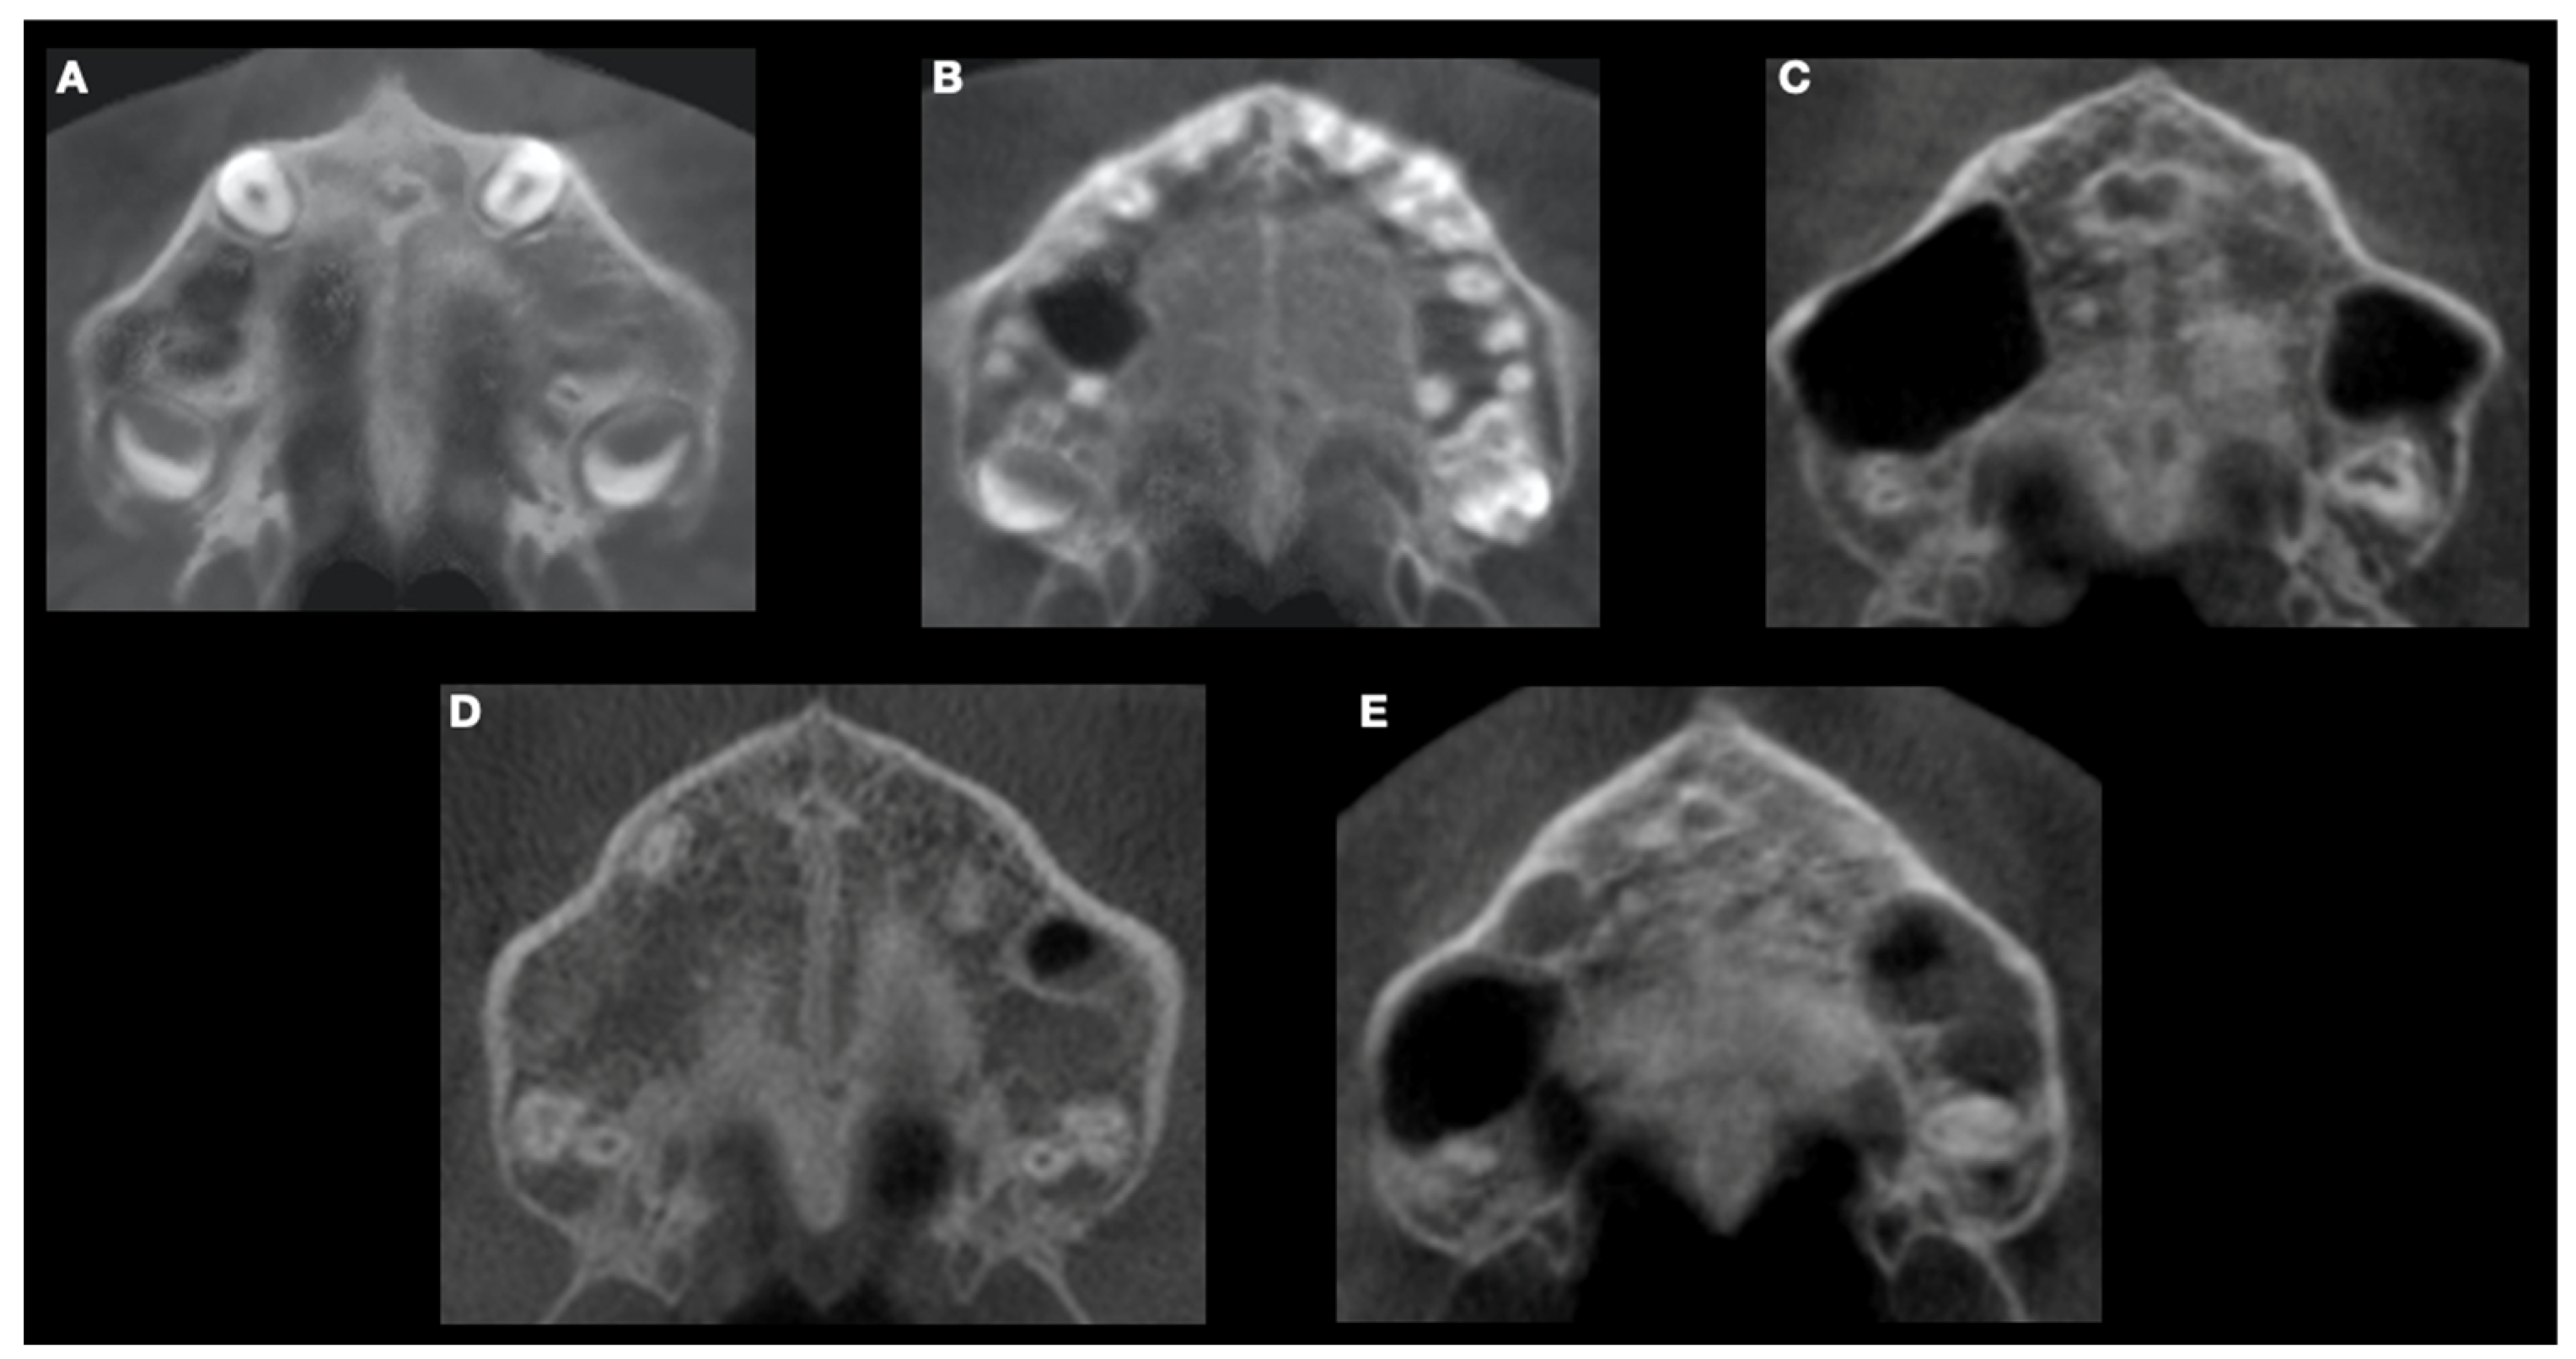

- Stage A refers to a relatively straight high-density line at the midline with no or little interdigitations;

- Stage B shows a scalloped high-density line at the midline with an irregular shape;

- Stage C presents two parallel, scalloped, high-density lines close to each other and separated in some areas by small low-density spaces;

- Stage D indicates a complete fusion in the palatine bone, where the midpalatal suture cannot be visualised;